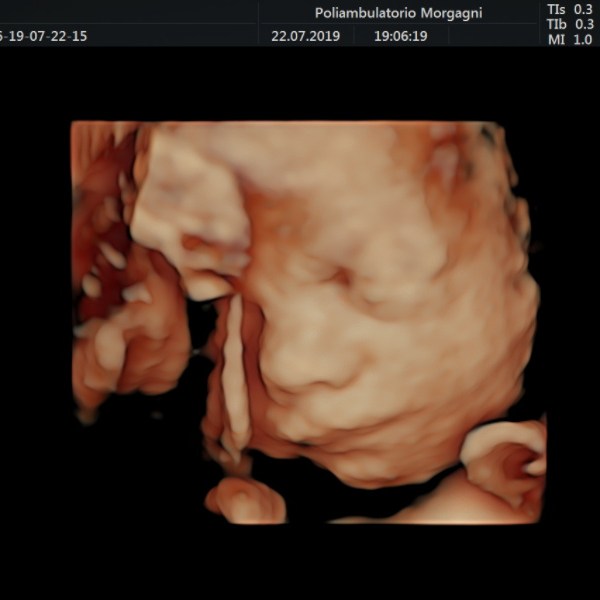

Il mese si conclude con l’ecografia di accrescimento da non eseguire troppo precocemente per ridurre il lasso di tempo fino al momento del parto.

Oltre la valutazione della biometria fetale, è importante controllare il benessere fetale con flussimetria a livello del cordone ombelicale e la quantità di liquido amniotico, vera cartina di tornasole del benessere fetale.